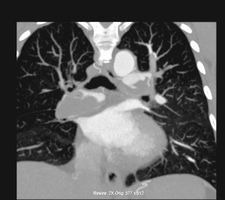

Wie wird die Lunge untersucht?

Die CT wird zur genauen Abklärung  von fokalen und diffusen Lungenerkrankungen (Tumore, Entzündungen, Fibrosen, Emphysem etc.) eingesetzt. Meist kommen die Patienten über unser Lungenzentrum.  Je nach Fragestellung werden verschiedene Techniken eingesetzt:

Das native CT wird  zur Abklärung von Tumoren, Fibrosen, Entzündungsprozessen  und Emphysemen eingesetzt, das generell mit 1mm dünnen Schichten als hoch aufgelöstes HRCT gefahren wird. Für das Kontrast-CT werden 50-60 ml Kontrastmittel vorher in die Armvene injiziert, dies dient der Erfassung der Vaskularisation von Tumoren und der besseren Abgrenzung von Lymphome bzw. Tumoren von Gefäßen.

In der CT-Angiographie werden die Pulmonalgefäße durch Bolustriggerung zeitgerecht kontrastiert, um Thromben (bei Lungenembolie) oder Gefäßstenosen (bei CTEPH) gezielt zu erfassen.  Für das Perfusions-CT werden beide Strahler und beide Detektoren benutzt, wobei der erste Strahler mit niedrigem kV-Wert (70 kV) und der zweite Strahler mit hohem kV-Wert (140 kV) angesteuert werden. Damit kann die lokale Konzentration von Jod im Kontrastmittel mit hoher lokaler und zeitlicher Auflösung an jedem Punkt in der Lunge bestimmt werden, wodurch Durchblutungsstudien für die gesamte Lunge möglich werden.